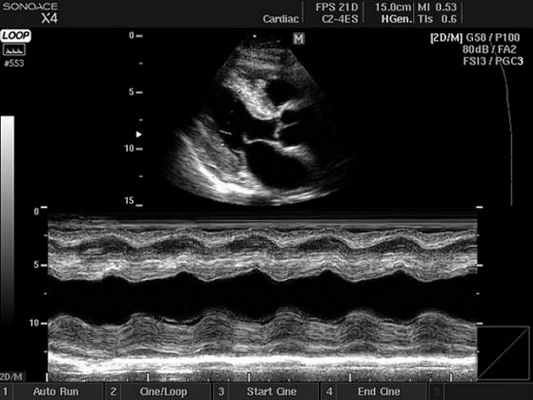

Основные режимы визуализации, применяемые при УЗИ сердца

Ультразвуковое исследование сердца в основном используется для получения двухмерного изображения этого органа и близлежащих магистральных сосудов. А также с помощью этой методики можно оценить скорость и направление кровотока, что требует применение эффекта Допплера. В зависимости от того, как обрабатывается и отображается на мониторе эхо-сигнал, различают следующие режимы ЭхоКГ:

- Двухмерный (2D режим). На монитор выводится изображение сердца в разрезе (в двух измерениях). Данный способ является основным при визуализации этого органа, позволяет детально рассмотреть анатомические отклонения и аномальные движения миокарда, клапанов.

- М-режим (M-mode). Это «усеченный» вариант предыдущего, при котором используется для анализа только одномерное изображение. Основное внимание уделяется одной из линий 2D трассировки, что позволяет более детально исследовать движения створок клапанов и сердечной мышцы.